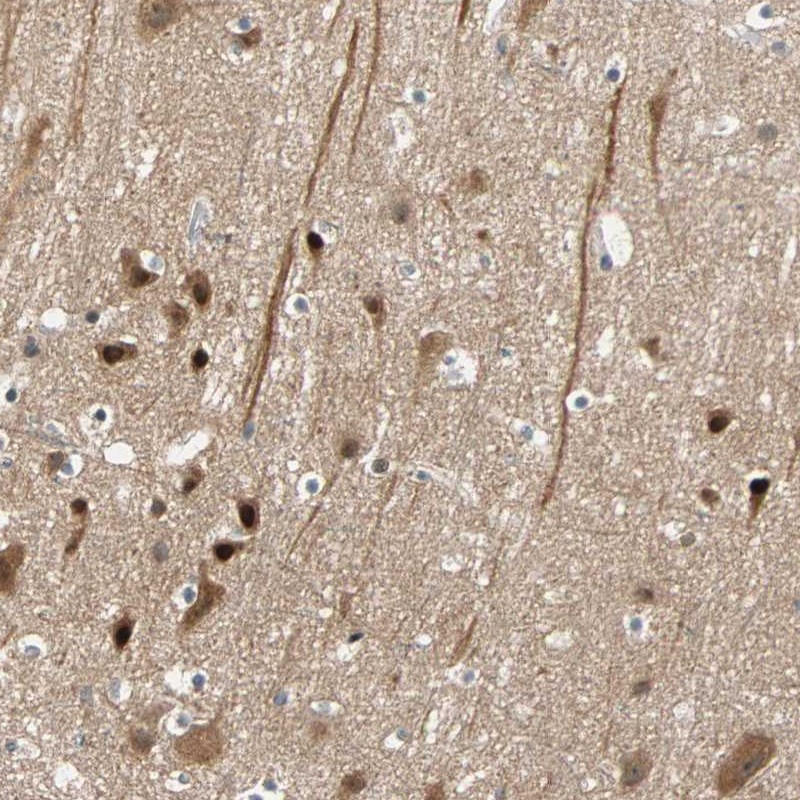

Immunohistochemical staining of human cerebral cortex shows strong nuclear and cytoplasmic positivity in neuronal cells.